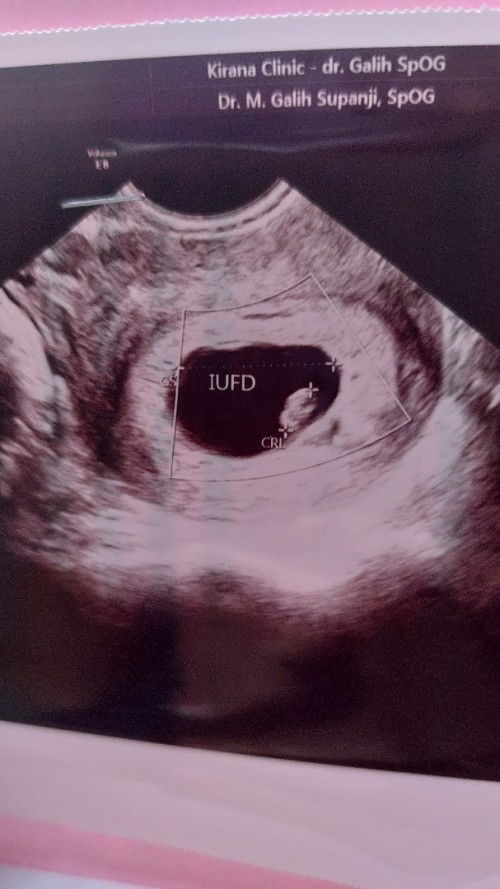

Kehamilan dinyatakan IUFD 12 minggu😭

Ass bunda2 saya mau minta saran nya, saya terakhir mens 6 april bulan mey saya gak mens juni tgl 3 saya kirain mens sedikit2 sampe la tgl 24 juni saya pikir uda gak wajar mens hampir 1 bulan, akhirnya saya cek ke dokter kandungan di usg katanya saya hamil uda 12 minggu tpi janin saya dinyatakan IUFD sempat setres saya karena uda 5 tahun menunggu😭katanya seminggu lagi kalo gak keluar mau di kuret, saya coba ke dokter lain dikasi penguat kandungan.disuru nunggu 1 bulan baru usg lagi..alhamdulillah sekarang tidak ngeplek lagi. Kalo saya tanya2 dan baca2 sumber dokter untuk dinyatakan IUFD itu usia kandungan paling muda 20 minggu sedangkan saya baru 12 minggu hitungan dokter wktu itu.. saya takut rasa nya mau ke dokter lagi buat tau hasil nya bun😭😭ada yg pengalaman kayak saya bun setelah dinyatakan janin IUFD apakah janin saya baik2 saja MINTA SARAN DAN PENDAPAT NYA BUNDA2 trimakasih🤗 Mohon doanya jg bunda🤗🤲

iufd itu kalau lebih dari 20minggu, kalau 12minggu itu masih disebut keguguran. ngga lah kalau iufd kan meninggal di dalem, ya ngga baik baik aja namanya juga udh meninggal. aku pernah iufd 28w anak pertama.